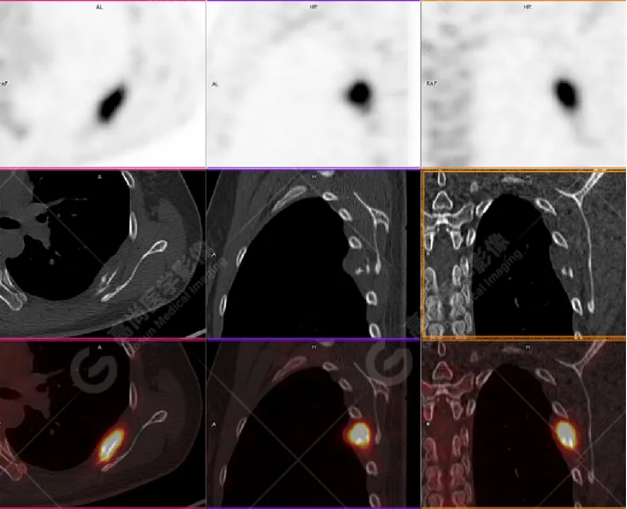

PET/CT影像圖

胸椎溶骨性骨質(zhì)破壞,F(xiàn)DG環(huán)狀代謝增高,SUVmax為4.0。

左側(cè)乳腺一軟組織結(jié)節(jié),F(xiàn)DG代謝增高,SUVmax為2.6。

最終診斷:左側(cè)乳腺癌伴胸椎單發(fā)骨轉(zhuǎn)移。